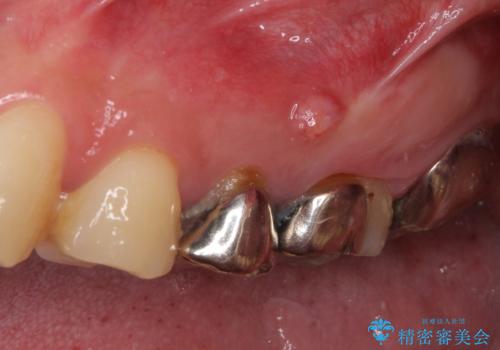

- 奥歯が痛いとのことで来院された患者様です。

歯肉に排膿の痕があり、叩いたり咬んだりすると痛みを感じていました。

根管治療を行い、その後フルジルコニアクラウンにて補綴することとしました。